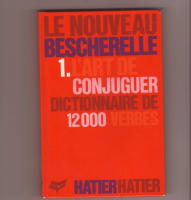

Mon plan de ttt était clair: on a fait des assainissements gingivaux début 2009 (parodontite généralisée perte osseuse entre 50 et 75%), suivis d'un grand bridge secteur 4 postérieur, tout allait bien lors d'un contrôle le 18/11 dernier (première rétro).

Deuxième rétro (c'est moi ou ça a progressé super vite?).